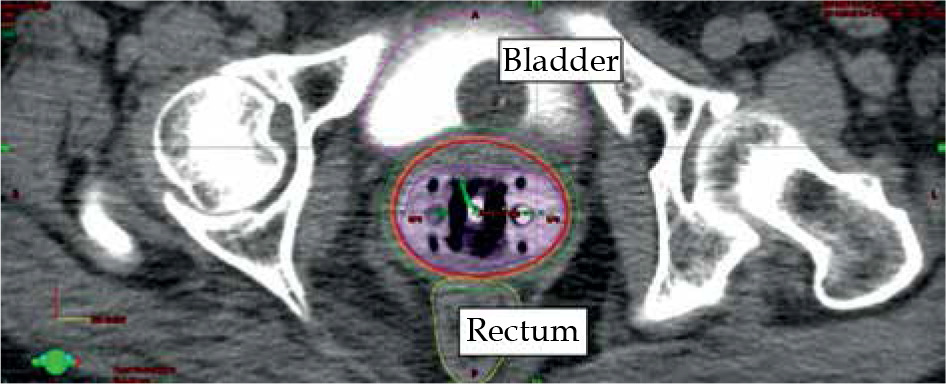

Fig. 3

Axial CT scan with applicator in place. Isodose levels of 650 cGy (orange) and 550 cGy (green) are presented